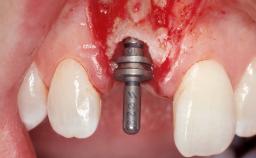

Immediate Flapless Placement of an Implant in a Maxillary Left Central Incisor Site

A 42-year-old female patient was referred to our clinic at the School of Dentistry of the University of São Paulo in November 2004, presenting a deficient restoration in the upper left central incisor. The clinical examination revealed no gingival retraction or any signs of gingival inflammation and, therefore, previous periodontal treatment was not considered. The patient presented a high lip line at full smile and a thin tissue biotype. This combination characterized a high-risk situation from an anatomic point of view, which required careful preoperative planning and cautious surgical execution.

| Placement Protocol | Immediate implant placement |

| Socket Morphology | Single-root socket |

| Socket Integrity | Sufficient, with intact bone walls |